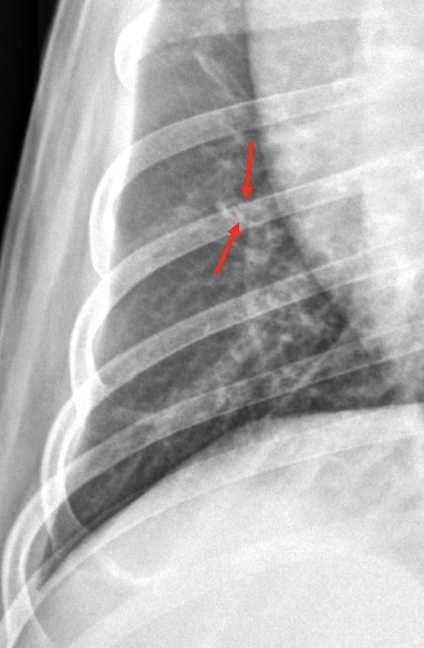

18

Q

Lung Pattern?

A

Alveolar

Air bronchogram